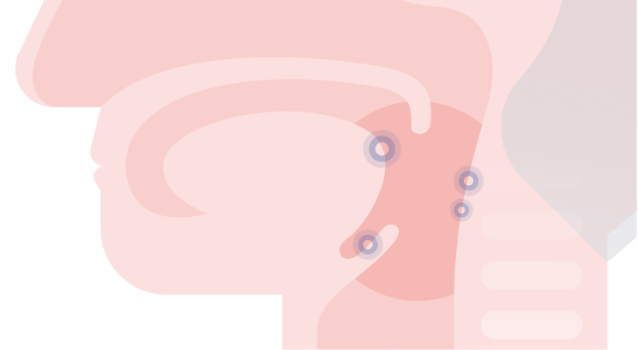

HPV-positieve orofarynxtumoren presenteren zich, vaker dan HPV-negatieve tumoren, als kleine (asymptomatische) tumoren die vaak al gemetastaseerd zijn naar de cervicale lymfeklieren.